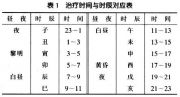

| 2021年7月26日 (一) 20:03 | 治疗时间与时辰对应表.jpg (文件) |  |

34 KB | 77921020 | Uploaded with SimpleBatchUpload | 3 |